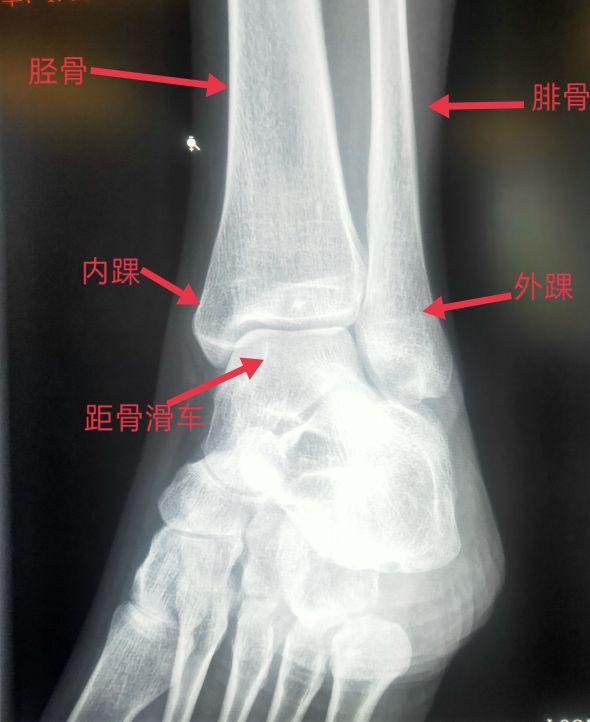

踝关节正位片上可以看到胫骨远端、腓骨远端、外踝、内踝、距骨滑车。

脚踝是哪个部位图解,脚踝是哪个部位图解视频(学习《X线读片指南》骨、关节系统——踝关节)